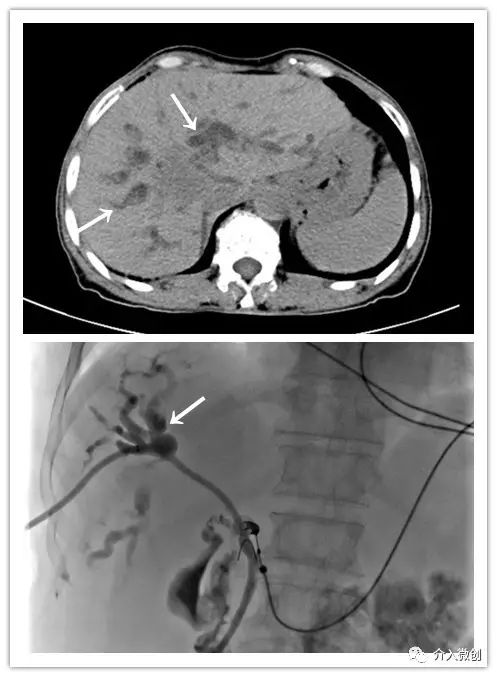

肝动脉化疗栓塞+经皮瘤内注药联合控制肝脏肿瘤

利用碘油化疗药物乳剂或载药微球微球栓塞肿瘤的供血动脉达到使肿瘤缺血缺氧坏死的目的,同时将化疗药带到肿瘤局部而起到缓慢释放、长期*伤杀**瘤细胞的作用。通俗地讲即通过栓塞阻断肿瘤营养血管,并联合化疗药物“饿死、毒死”肿瘤细胞。